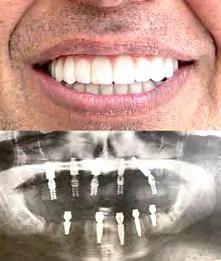

Лучшее качество услуг и материалов по разумной цене! Консультация и 3D снимок в подарок.

Установка одного импланта от

Одна из недавних операций:

Все-на-5-ти имплантах + несъемные зубы за 1 день

Высококлассные услуги по Зубной Имплантации в современной клинике, лимиторованной на установку имплантов.

* - установка 1 (одного) импланта не включая абатмент и коронку. Имплантация будет производится одним из специалистов клиники под руководством доктора Александра Антипова, челюстно-лицевого хирурга. Цена указана для пациентов, оплачивающих наличными.

(916) 827-3605

# 12 (2023) • 25 июня Газета «Диаспора» – все о нас с вами ПО ВОПРОСАМ РАЗМЕЩЕНИЯ РЕКЛАМЫ ОБРАЩАЙТЕСЬ ПО ТЕЛЕФОНУ: (916) 487-9701 или (916) 705-0739 10 Замещение всех зубов на 4-х, 6-ти имплантах Одиночные импланты Несколько имплантов ИМПЛАНТАЦИЯ ЗУБОВ